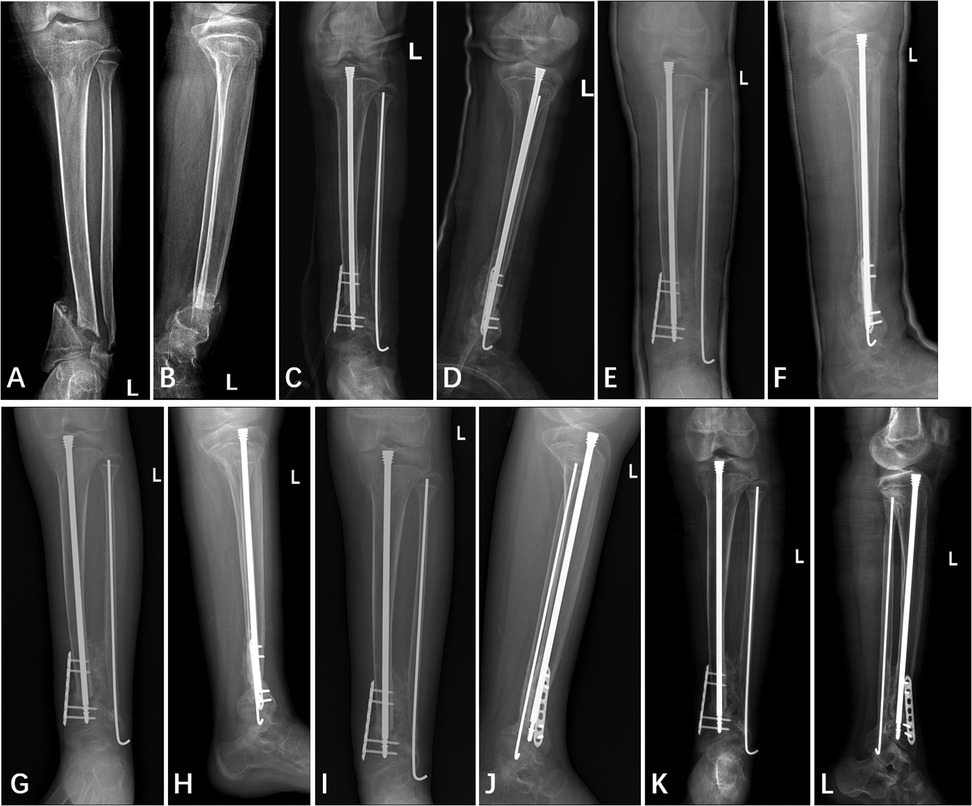

The patient underwent the first stage of “cross-union” surgery at our institution. Based on preoperative imaging localization (Figures 4A,B), a longitudinal incision approximately 10 cm in length was made over the anterior aspect of the left lower leg at the site of the nonunion. Anterior and deep posterior fasciotomy and muscle reflection to expose tibia, interosseous membrane, and fibula, allowed procedures to be performed under direct vision without damage to the neurovascular bundles. Fracture ends were separated, fibrous connections and sclerotic bone were removed, over the planned length of the cross-union. The medullary cavity of the tibia and fibula was penetrated to prepare for internal fixation implantation. During the preoperative physical examination, we identified an Achilles tendon contracture on the left side, which was further confirmed during the surgery. Therefore, a second incision was made posteriorly over the distal left lower leg to perform percutaneous lengthening of the left Achilles tendon. Subsequently, a customized Fassier-Duval telescopic nail is inserted to maintain tibial length and accommodate future bone growth, the male end locked into the distal epiphysis and the female end screwed into the proximal epiphysis. A seven-hole locking plate and four screws were used to fix the distal tibia to achieve enhanced local stability and prevent rotation. A 2.5 mm Kirschner wire was used for intramedullary fixation of the fibula to further reinforce local stability. A third incision, approximately 8 cm long, was made over the iliac crest. A periosteal graft is harvested from the undersurface of the iliacus muscle. It is then expanded by passing it through the skin graft mesher. Decancellousization of the ilium is done by first splitting the two cortical tables of the ilium down to the roof of the acetabulum, triradiate cartilage, sciatic notch, posterior spines and sacro-iliac joint. The periosteal graft is wrapped around the fracture ends and bone morphogenic protein-2 (BMP2) collagen sponges are inserted overtop the posterior muscles behind the tibia and fibula. The cancellous bone is inserted between the tibia and fibula. Another BMP2 sponges are placed overtop the bone graft. The anterior muscles lie over the BMP2, ultimately forming a five-layer sandwich structure of muscle–BMP2–graft–BMP2–muscle (8, 9). Considering the potential for significant postoperative bleeding, a long-leg posterior splint was applied with a drainage tube in place immediately following surgery (Figures 4C,D). The drain was removed 7 days postoperatively, at which point the immobilization was converted to a long-leg cylindrical cast. The patient was followed up monthly with radiographic examination. During the casting period, weight bearing on the affected limb was strictly prohibited. No specify drug other than antibiotic was used.

Figure 4. Anterior and lateral x-ray film of left tibia and fibula (A,B) one day pre-operation, (C,D) one day post-operation, (E,F) two months post-operation, (G,H) four months post-operation, (I,J) five months post-operation, and (K,L) twelve months post-operation.

Callus began to appear approximately two months after surgery (Figures 4E,F). The decision to remove the cast at four months was based primarily on the radiographic evidence of healing, specifically, the observation of continuous callus formation bridging the non-union site (Figures 4G,H). The patient was allowed to start protected weight bearing with crutches and an orthosis after cast removal, and progressed to independent weight bearing without assistance by approximately 5 months postoperatively. At the final follow-up 12 months postoperatively, x-rays revealed a stable “cross-union” bone connection at the distal ends of the tibia and fibula, with no occurrence of refracture or other complications (Figures 4I,J). The Radiographic Union Score for Tibial fractures (RUST) was calculated using standard anterior-posterior and lateral views (Table 2). At the two-year postoperative mark, the patient did not return to our institution for radiographic follow-up. However, a telephone survey was conducted to assess the recovery of her lower extremity motor function. Functional recovery assessment was performed using the Olerud Molander Ankle Score (OMAS) (Table 3).